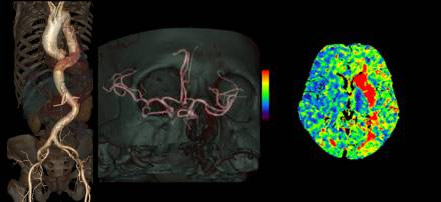

輪切りにする厚みは、最小0.625mmと細かい(薄い)画像が得られます。

これをコンピュータにより重ね合わせて、下記縦切り画像や3D画像を作成し診断に貢献させます。

当院では3台の64列CT装置を設置し検査を行っています。CT検査における被ばく低減と画質向上を目的とし、3台ともすべてに逐次近似法を応用した画像再構成法を導入しています。これにより従来と同程度の画像であれば従来のX線量の半分以下での画像化を、従来と同じX線量であればさらに高画質にすることが可能となりました。また、2022年には3次元画像解析システムSYNAPSE VINCENT(富士フィルム社製)を導入し、様々な診療科のニーズに対応しております。

当院での最高機種にあたるCTは、人体を透過したX線を検出する部分に新素材を採用し、これにより高精細な画像情報を提供するとともに、患者さんの被ばく低減も実現した装置です。アーチファクトやノイズも軽減され、細かい部分がはっきりと見えることにより内耳周辺の細かい骨の構造や血管情報、心臓では特にステント内腔の評価に優れています。また1つの管球で、2つの管電圧を高速で切り替えることにより、2つのエネルギーでの撮影が可能です。これにより画像コントラストの増強や金属によるアーチファクトの低減、骨、石灰化の分離により血管内狭窄の評価が期待されます。